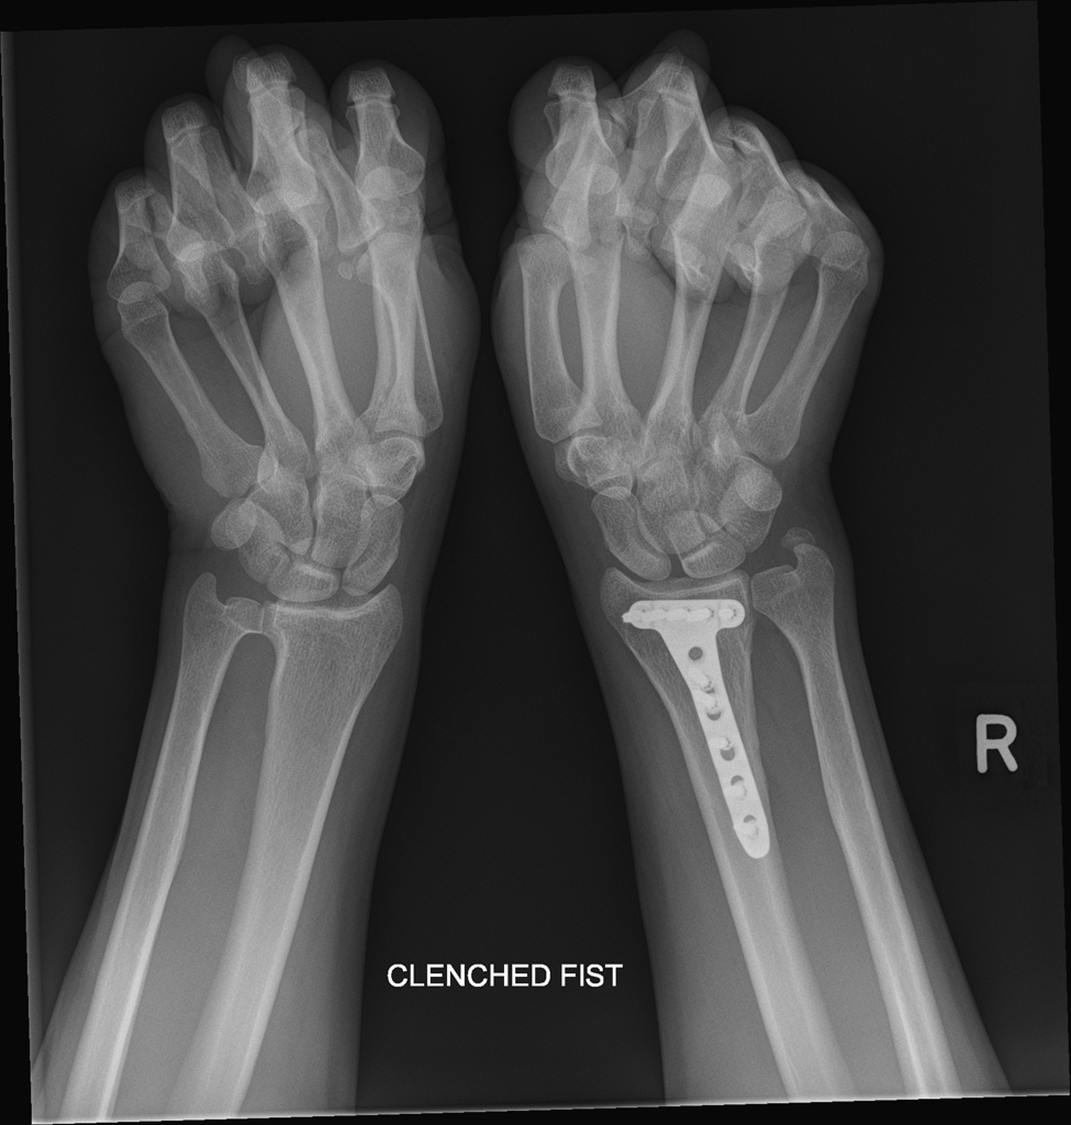

What view is this?

clenched fist view

What’s another name for clenched fist view

stress view PA

What is the clenched fist view used for

identify scapho-lunate dissociations

What does this image show

gap between the scaphoid and lunate